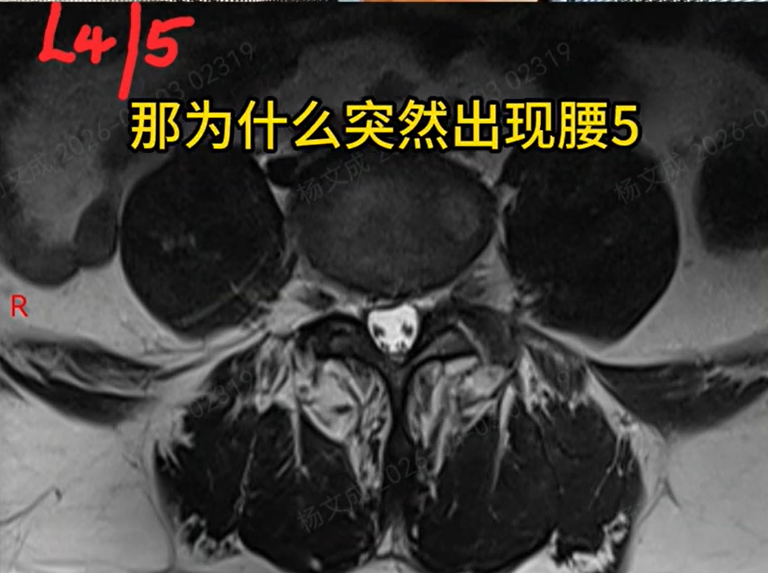

再看影像学检查:提示腰4椎体Ⅰ度滑脱。

患者腰4滑脱属于稳定型,既没有明显椎管狭窄,这个节段也没有椎间盘突出,

为什么会突然出现腰5神经根样的损害表现?会不会另有原因?

带着这个疑点,杨文成和团队反复、细致研读腰椎MRI和CT,终于在腰3/4后外侧位置,发现了一个非常微小的椎间盘突出。

腰3/4突出通常压迫的是腰4神经根,和患者表现出的症状定位并不完全匹配。

难道是存在少见的神经走行变异?